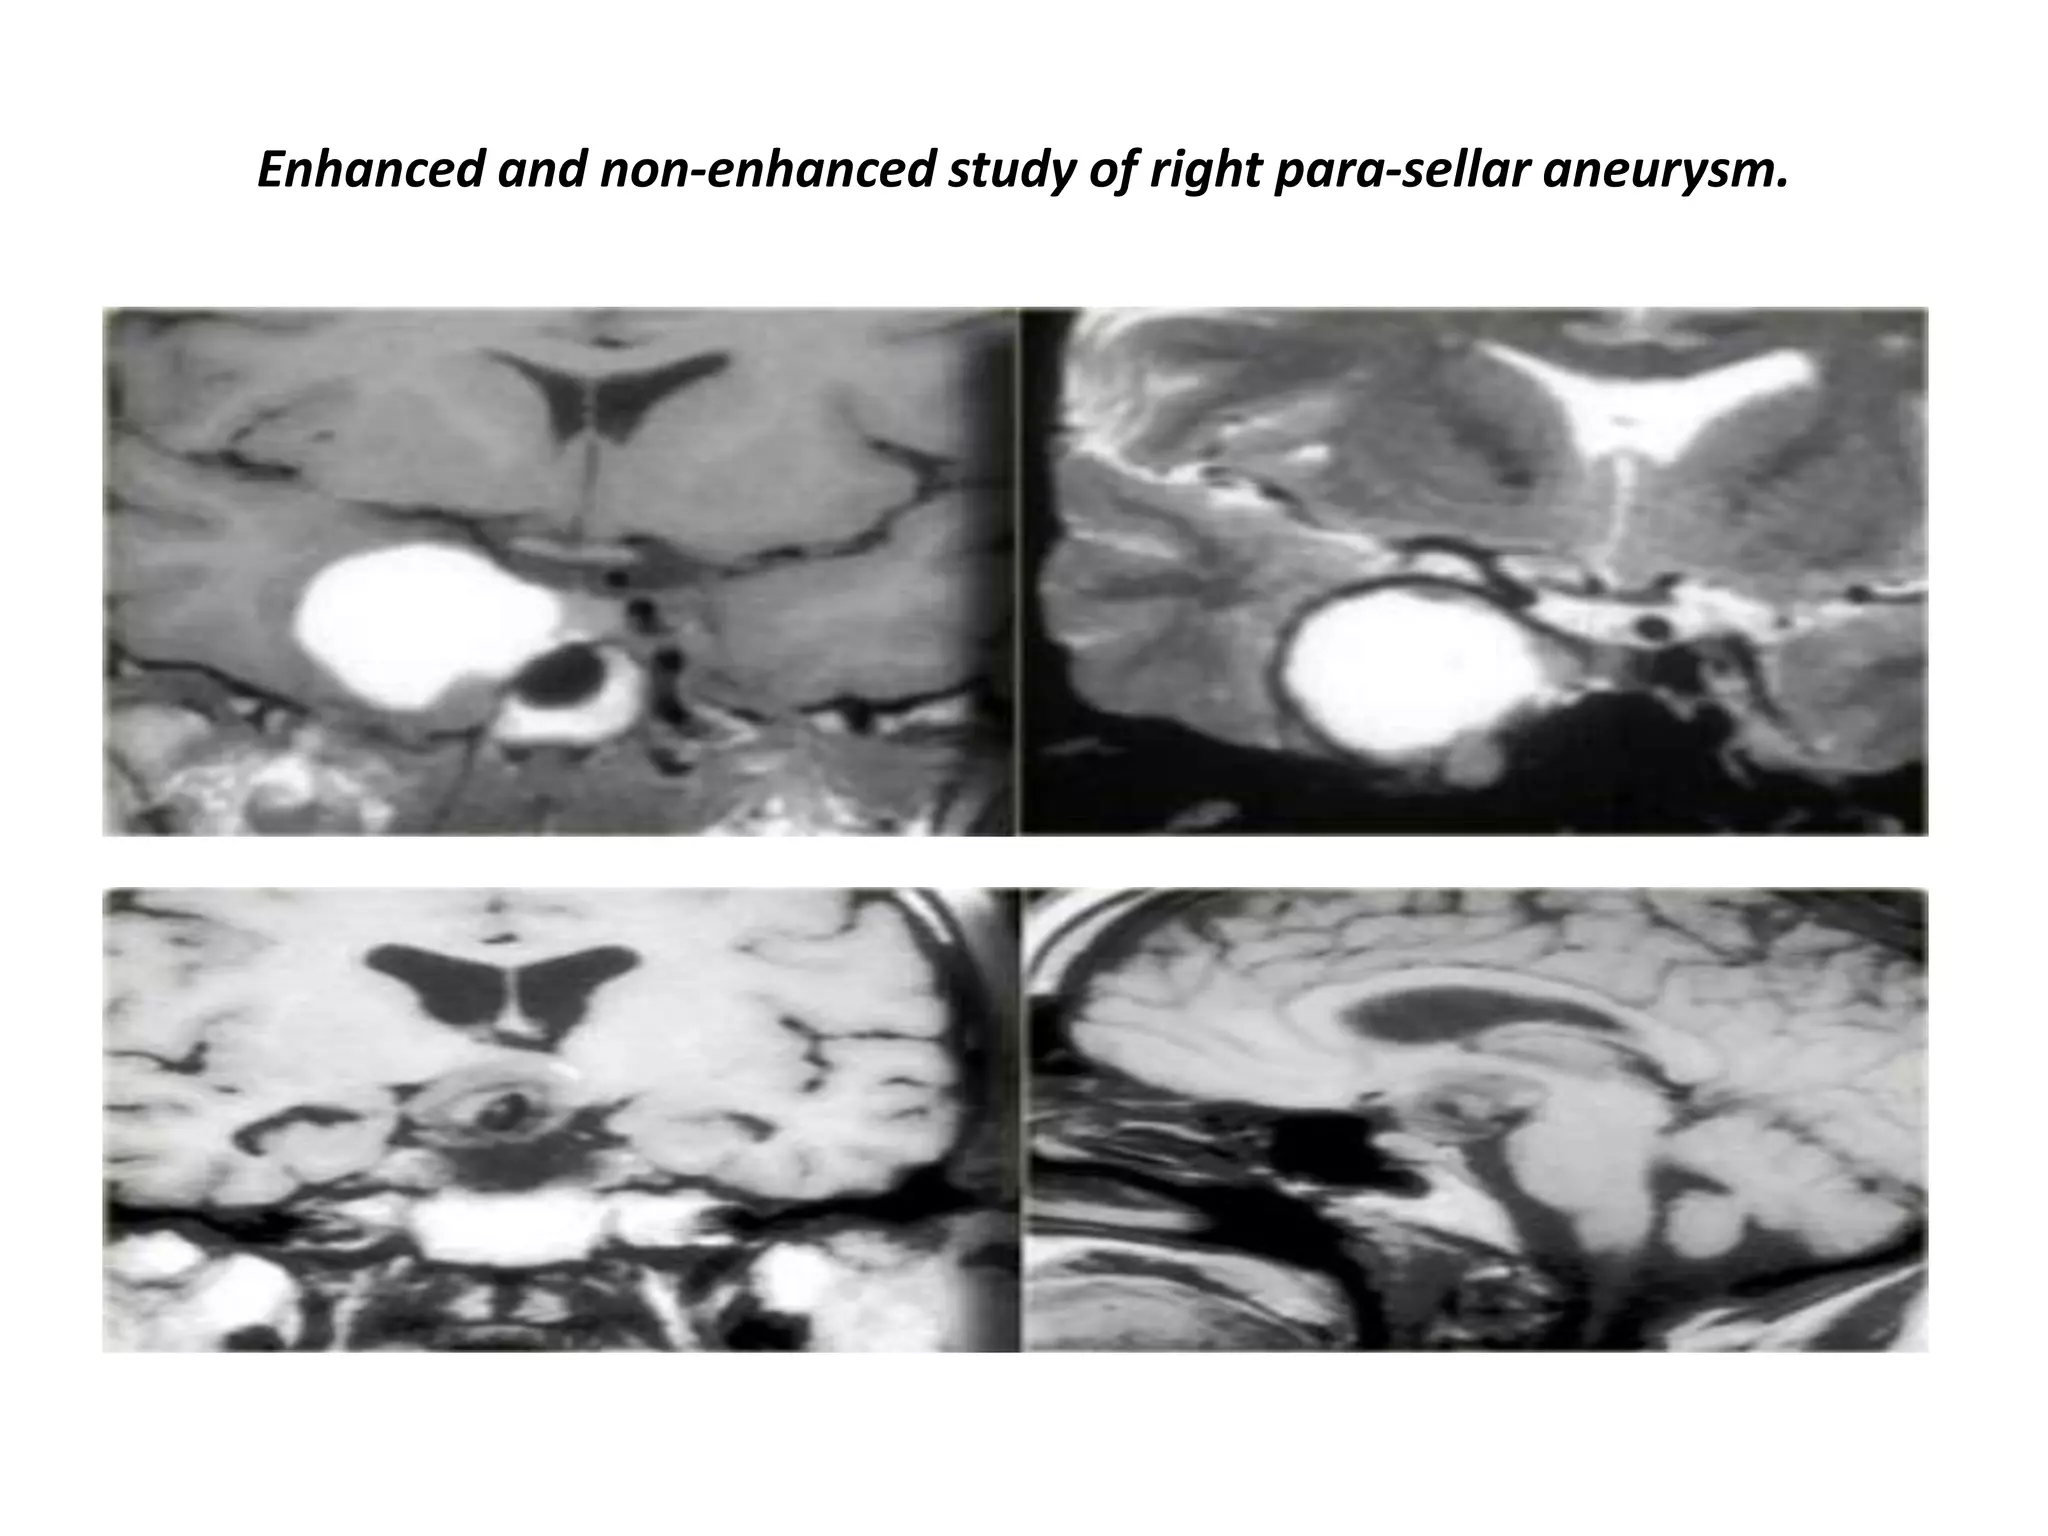

Right para-sellar partially thrombosed aneurysm.

Aneurysm of right para-sellar region with partially thrombosed aneurysm.

Enhanced and non-enhanced study of right para-sellar aneurysm.

The mass is predominantly black and there is a large flow artifact running in the phase-encoding direction.

These findings correspond to rapid blood flow, and the mass must therefore be an aneurysm